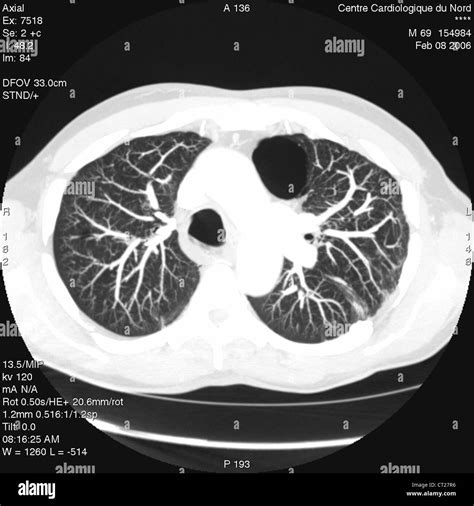

Diagnostic Procedures

Diagnosis begins with a thorough medical history and physical examination. However, imaging is essential to confirm Bullous Lung Disease. High-resolution Computed Tomography (HRCT) is considered the gold standard for visualizing bullae. It allows physicians to determine if the bullae are localized or widespread and whether they are compressing functional lung tissue. Pulmonary function tests (PFTs) are also conducted to measure lung capacity and identify the degree of airflow obstruction.

While often associated with emphysema, bullae can develop through various mechanisms. The lung tissue essentially loses its internal architecture, leading to areas of over-inflation. When these areas become large enough to compress healthy surrounding tissue, the condition is referred to as giant bullous emphysema, or Vanishing Lung Syndrome, in extreme cases.

⚠️ Note: Always consult with a pulmonologist to undergo diagnostic imaging, such as a CT scan, as chest X-rays may not always reveal the full extent of the bullae.